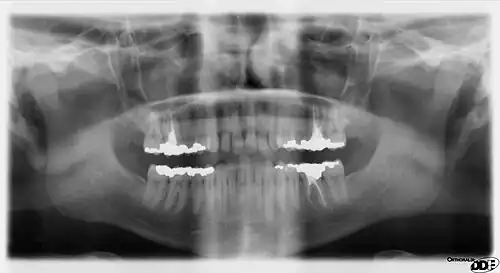

Panoramic radiograph

A dental panoramic radiograph, showing the maxilla and mandible, all the teeth including the "wisdom teeth," the frontal and maxillary sinuses, the nasal cavity and the temporomandibular joint and other near by head and neck anatomy.